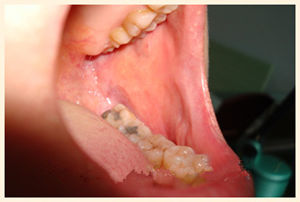

(朱先生治疗前的口腔内壁状态)

(朱先生治疗后的口腔内壁状态)